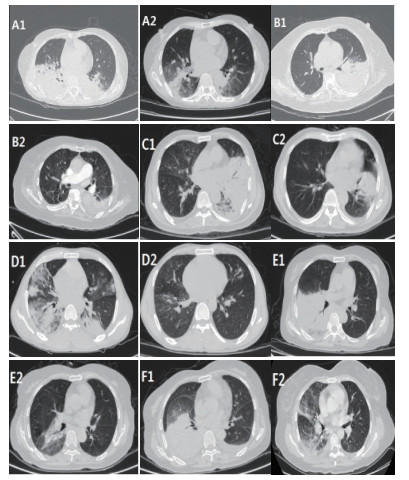

4例患者白细胞正常,2例患者出现升高;4例患者中性粒细胞比例升高,2例正常;5例患者ESR不同程度升高(32~88 mm/h);6例患者Hs-CRP升高明显;3例PCT升高明显,3例轻度升高;6例患者均出现转氨酶异常;3例患者出现心功能不全,4例出现轻度心肌损伤;1例患者出现肾功能不全。5例患者CD3+、CD4+细胞数减少,表现为细胞免疫抑制。患者胸部影像学检查结果表现为渗出性病变,实变为主,可累及多个肺叶,肺下叶受累较常见,病灶进展迅速,后期可出现少许胸腔积液,见表 12图 1

A1、A2;B1、B2;C1、C2;D1、D2;E1、E2;F1、F2分别为病例1~6患者治疗前后胸部CT变化情况,患者表现为大片状实变影,经治疗后胸部CT可见病灶明显吸收。 图 1 6例患者胸部CT表现

鹦鹉热本质上是一种全身性疾病,以呼吸系统感染为主,也可累及肝脏、肾脏、血液、循环及中枢神经等系统,导致多器官功能不全[9-10]。Chen等[6]报道的9例重症鹦鹉热肺炎患者中均出现畏寒发热、咳嗽、乏力及呼吸衰竭等症状,多个患者出现头晕、肌痛并发展为脓毒血症;实验室检查提示白细胞正常或轻度升高,中性粒细胞比例升高,CRP、PCT升高明显,部分患者出现心肌酶、肝酶升高,这与本研究报道的结果基本一致。患者均表现有高热及CRP明显升高,但白细胞数正常或轻度升高,这是与细菌性肺炎鉴别的一个重要特征。影像学方面,该疾病尚缺乏特异性表现,胸部X线最常见表现为单个下肺叶改变,胸部CT显示实变结节与周围磨玻璃改变[1]。本研究所报道的6例病例胸部CT均以实变为主要征象,多为大片实变,以肺下叶受累明显,与Coutts等[11]、Kong等[12]报道相一致。而Gu等[7]报道的5例鹦鹉热衣原体肺炎中2例以肺下叶实变为主,2例以右肺上叶实变为主,1例起初以右上肺实变为主,后病情加重,胸部CT显示双肺弥漫病灶,以双下肺大片实变为主。出现以上差异,可能与纳入研究病例的病情严重程度有关。